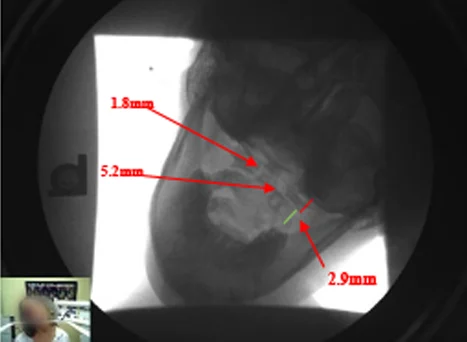

DMX motion X-rays can be analyzed using Computerized Radiographic Mensuration Analysis (CRMA) to provide objective, repeatable measurements of cervical motion. This turns a motion study into documented findings that can be reviewed, compared, and referenced rather than relying on description alone.

When appropriate, CRMA-style mensuration is used to document:

• Translation (movement between vertebrae measured in millimeters)

• Angular change (changes in alignment/angulation during motion)

• Abnormal motion patterns consistent with cervical ligament injury and instability

These objective measurements help define the extent of abnormal motion and support clearer medical documentation of ligament injury and ligament damage.